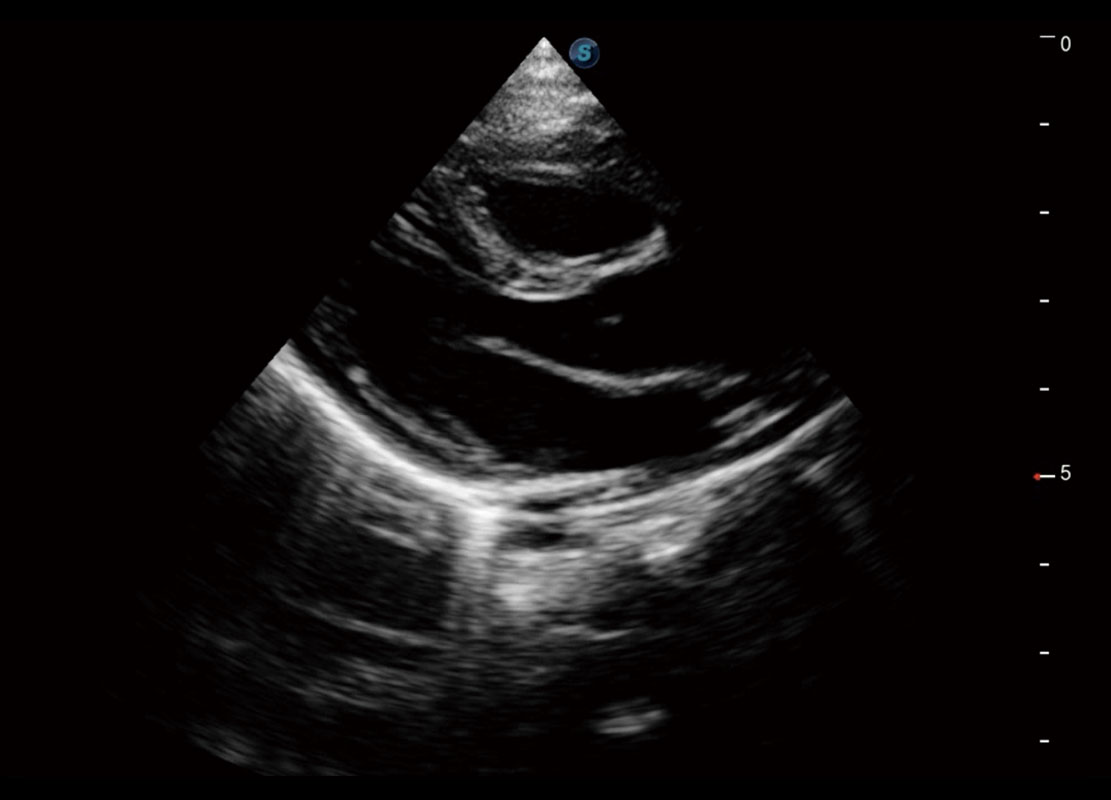

P60搭载一系列胎儿心脏成像技术,实现精细的胎儿心脏评估。

四腔切面

胎心容积成像

新生儿心脏